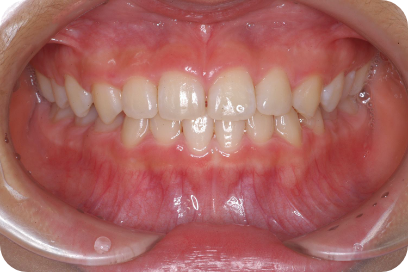

Nさん

Before

After

- 形態:

- 機能:

- 期間や回数:

- 治療費:

- メリット:

- リスクと副作用: